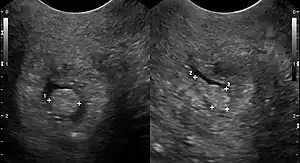

Cervical polyp on ultrasound